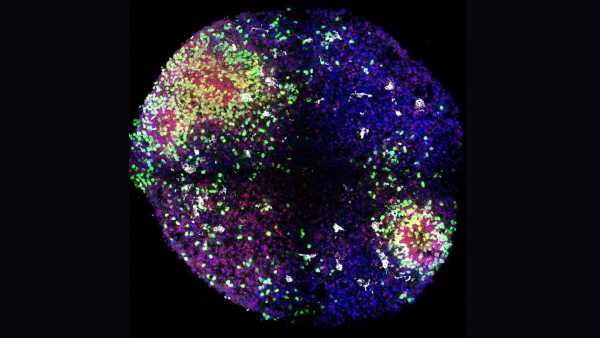

Щоб дослідити імунну систему в цих групах, команда використала секвенування РНК окремих клітин, що дозволило їм дослідити тип генетичного матеріалу, який називається РНК, всередині кожної імунної клітини. РНК відображає, які білки виробляє клітина в певний момент. Команда також використовувала високовимірну плазмову протеоміку, яка картографує білки, що циркулюють у крові, та спектральну проточну цитометрію, яка ідентифікує та підраховує імунні клітини за їхніми молекулярними «відбитками пальців».

Дослідники виявили суттєві відмінності в Т-клітинах пам'яті — імунних клітинах, які «пам'ятають» минулі інфекції та допомагають організму швидше реагувати наступного разу, коли з'являється патоген.

У людей похилого віку зростаюча кількість Т-клітин пам'яті переходить у стан, який змінює їхню реакцію на загрози — змінюючи їхню взаємодію з В-клітинами. Дослідження показало, що коли Т-клітини пам'яті не працюють належним чином, В-клітини стають менш ефективними у виробленні антитіл у відповідь на інфекції або вакцини. Тим часом Т-клітини пам'яті молодих людей вміло реагували швидко та посилювали очікувану антитільну відповідь.